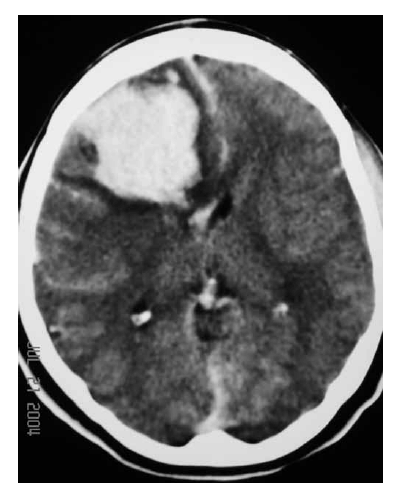

Uma mulher de 29 anos de idade teve sua gestação interrompida com 35 semanas, mediante parto cesariano, por ter apresentado quadro compatível com a doença hipertensiva específica da gravidez. No quinto dia de pós-operatório, apresentou importante dor de cabeça seguida de crises convulsivas; na avaliação laboratorial, foram atestadas plaquetopenia e alteração da função hepática. Ela foi levada à unidade de terapia intensiva, onde o plantonista observou hemiparesia esquerda e solicitou uma tomografia de crânio sem contraste, que é reproduzida abaixo.

Com base nessas informações, julgue os itens que se seguem.

O exame de neuroimagem evidencia volumoso abscesso cerebral.